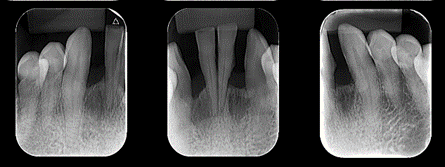

Um paciente procurou tratamento protético reabilitador com queixa dos dentes 31 e 41 que estavam abalados. Ao exame clínico e radiográfico, notou-se mobilidade dos dentes, doença periodontal ativa e perda óssea.

Avaliamos o espaço mésio-distal entre os dentes 33 e 43 e constatamos a ausência de distância para a colocação de implantes individualizados. Assim sendo, optamos pela instalação de dois implantes Veloce CM de diâmetro 3.3 e pilares do tipo micro-cônico para a solução clínica.